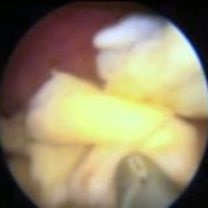

Hysteroskopie je vhodná také pro odstranění drobných částí po proběhlém porodu nebo potratu, pokud v děloze přetrvávají např. zbytky placenty. Do určitého množství to lze provést i ambulantně. Operační nástroj je patrný v dolní části snímku.